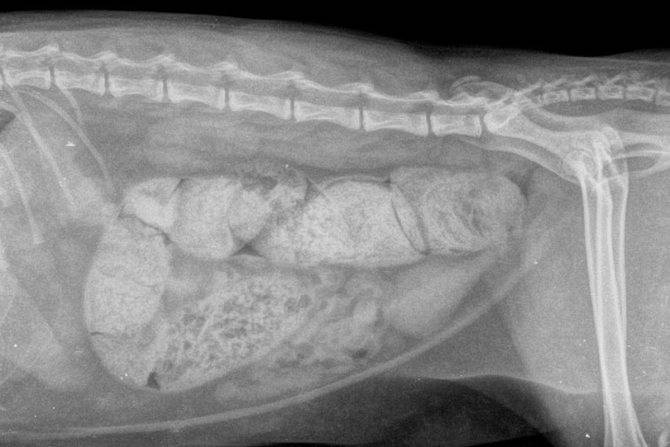

Для уточнения предварительного диагноза ветеринар может назначить:

- рентгенографию;

Рентген копростаза собак